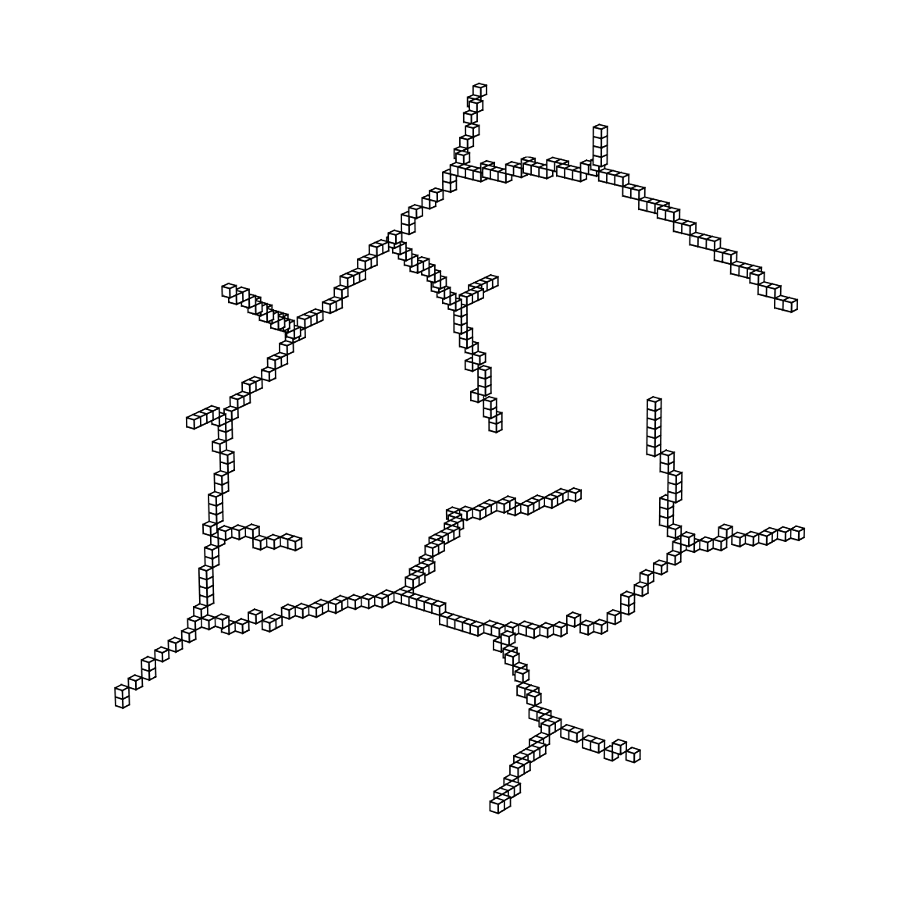

3.2 Connected Geodesic Paths as Vascular Tree

Representative examples of degraded synthetic images from SVT and the respective GT are shown in fig. 4 together with the connected graphs extracted by VTrails. Analogously, the same set of images are reported for the real images TOF and CTA in fig. 4. Qualitatively, the extracted set of connected geodesic paths shows remarkable matching with the provided GT in all cases. First, we verify the acyclic nature of the graph. We found no cycles, degenerate graphs and unconnected nodes, meaning that the extracted connected geodesic paths represent a connected geodesic tree. Precision and recall are then evaluated for the identified branches. Also, error distances are determined as the connected tree’s binary distance map evaluated at GT. Average errors () precision and recall are reported (meanSD) in table 1. Note that no pruning of any spurious branches is performed in the analysis.